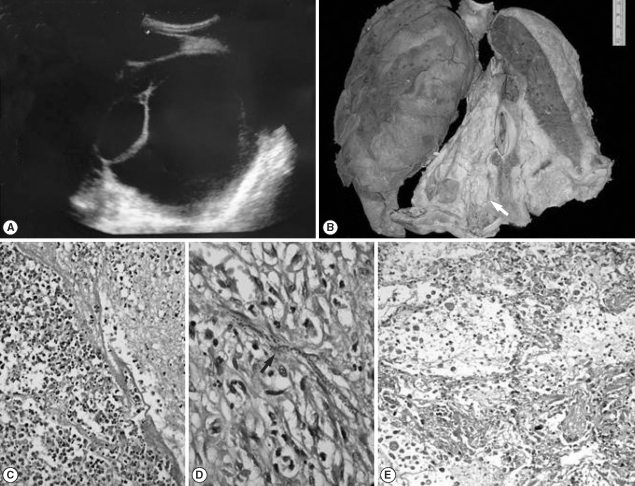

A 21-year-old male presented with progressive breathlessness for the past 2 months with pain in the right upper quadrant of the abdomen for 4 days duration. He also complained of cough with scanty expectoration and high grade fever of similar duration. There was no history of pedal edema, decreased urine output, abdominal distention, chest pain, or palpitation. On examination, he had tachycardia with raised blood pressure (160/90 mm of Hg), but the other vitals were stable. The jugular venous pressure (JVP) was normal. There was tenderness in the right upper quadrant with hepatomegaly. The spleen was not palpable and no ascitis was noted. Cardiovascular system examination revealed a loud S2 with a pansystolic murmur in the tricuspid area. Chest examination revealed bilateral crepitations. Investigations revealed leucocytosis (TLC-16,800) with mild eosinophilia (16%). Renal function tests were deranged with raised blood urea (75 mg/dl) and serum creatinine (1 mg/dl). Chest X-ray showed an opaque left hemithorax, and on ultrasonography a large, well defined, anechoic cystic lesion was seen occupying the entire left hemithorax with multiple septations (Fig. 1A), suggesting the possibility of a hydatid cyst. The liver span was 12 cm with normal echotexture. Microscopic examinations of the pleural fluid revealed 2,800 pus cells with 2 mg/dl sugar and 6 g/dl proteins. The patient was treated with injection of Lasix and antibiotics; however, his condition soon deteriorated and he succumbed to his illness with cardiorespiratory arrest.

A partial autopsy was performed following an informed consent. Mild bilateral scrotal sac enlargement was noted. There was bilateral pleural effusion with 1,500 ml of straw colored fluid and bilateral hydrocoele with 20 ml of fluid in the scrotal sac. Both lungs weighed 730 g, and there was marked pleuritis with fibrinous tags (left > right). A large multi-loculated pleural based cyst (10 × 8 × 3 cm) filled with thick greenish material was present on the left side (Fig. 1B). Multiple tiny nodular lesions (4-5 mm) were palpable in the rest of the lung parenchyma. Microscopically, the cyst was confirmed to be a loculated empyema with outer fibrous wall, scattered giant cells, and the lumen filled with fibrin-rich acute inflammatory exudate chiefly comprising of eosinophils (Fig. 1C). Also seen in the cavity wall were many sheathed microfilariae of Wuchereria bancrofti (with absence of characteristic fine nuclei in the tail) (Fig. 1D). Other areas revealed features of tropical pulmonary eosinophilia (TPE) with eosinophilic alveolitis and bronchitis (Fig. 1E). A large thrombus was noted in the main pulmonary artery with large areas of infarction, and adjacent areas showed presence of heart failure cells within the alveoli.

Microfilariae are trapped and destroyed in the lung by antibody-dependent, cell-mediated cytotoxicity involving eosinophils, and these degenerating worms release somatic allergens that bind specific cell-bound IgE and thereby trigger the release of vasoactive and inflammatory molecules by lung basophils and mast cells [6]. Microfilariae and degenerated worm fragments are present in lung nodules of patients with TPE, thus providing support to this pathogenetic mechanism [7]. Microfilariae were detected within the fibrous wall of the lung cyst in the index case with eosinophils and fibrin-rich inflammatory exudate surrounding it. However, their presence seems to be incidental and not a causative mechanism for cyst formation and empyema.